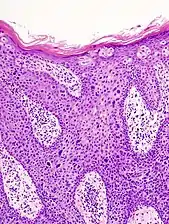

In situ disease

Bowen's disease is essentially equivalent to and used interchangeably with cSCC in situ, when not having invaded through the basement membrane.[12] Depending on source, it is classified as precancerous[13] or cSCC in situ (technically cancerous but non-invasive).[47][48] In cSCC in situ (Bowen's disease), atypical squamous cells proliferate through the whole thickness of the epidermis.[12] The entire tumor is confined to the epidermis and does not invade into the dermis.[12] The cells are often highly atypical under the microscope, and may in fact look more unusual than the cells of some invasive squamous-cell carcinomas.[12]